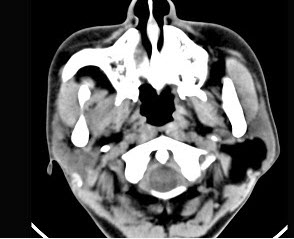

男性38岁,左侧腮腺渐进性肿大一年,无压痛,CT扫描如图所示,请选择正确的描述和结论()。

A、左侧腮腺区见低密度肿块,CT值约为-200Hu

B、肿块边缘清楚,未见邻近结构受侵

C、考虑为囊肿

D、考虑为脂肪瘤

E、考虑为血管瘤

A,B,D